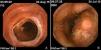

La EICH se puede presentar de diferentes maneras en el intestino delgado, afectándolo por segmentos o en su totalidad. Los principales hallazgos en este órgano son edema, eritema, erosiones, úlceras y hemorragia5. La cápsula endoscópica (CE) es una herramienta no invasiva que nos permite observar la totalidad del intestino delgado6 y que puede ser de gran utilidad para agilizar el diagnóstico de la EICH. El objetivo de este reporte es dar a conocer la utilidad de la CE en pacientes con sospecha de EICH gastrointestinal.

Caso 1Paciente varón de 25 años de edad, con diagnóstico de hemoglobinuria paroxística nocturna. El 14 de mayo del 2015 se le realiza TACH. A los 30 días presenta distensión abdominal, náusea y diarrea. Se le solicita panendoscopia y colonoscopia con toma de biopsias. Al mismo tiempo, se le coloca una CE encontrando en intestino delgado aplanamiento de vellosidades, edema de la mucosa y pérdida del patrón vascular, además en algunos segmentos se observa denudación de la mucosa, úlceras cubiertas de fibrina, así como sangre fresca y coágulos. La CE fue avanzada a duodeno por endoscopia posterior a permanecer 6h en el estómago. Mediante histopatología se corrobora el diagnóstico de EICH, una semana después. Al no haber respuesta inicial se da la segunda línea de tratamiento. Responde adecuadamente por lo que es dado de alta.

Caso 2Paciente varón de 37 años de edad, con diagnóstico de leucemia mieloide crónica. Se realiza TACH el 30 de junio del 2015. A los 29 días del trasplante ingresa por presentar diarrea, náusea y vómito. Se realiza panendoscopia y colonoscopia con toma de biopsias. Al mismo tiempo se coloca CE identificando en todo el intestino delgado aplanamiento de vellosidades, denudación de la mucosa, úlceras que provocaban zonas de estenosis y sangrado activo. Histopatología confirma el diagnóstico de EICH 10 días después. Actualmente, en segunda línea de tratamiento refractario al manejo de esteroide.

Caso 3Paciente varón de 45 años de edad con diagnóstico de leucemia mielomonocítica aguda, el 4 de junio del 2015 se realiza TACH. En el día 54 posterior al trasplante presenta dolor abdominal tipo cólico intermitente con diarrea, náusea, vómito e intolerancia a la vía oral. Dos días después se presenta hematoquecia hasta en 17 ocasiones. Se le realiza panendoscopia y colonoscopia con toma de biopsias. Se coloca CE observando en yeyuno e íleon acortamiento de vellosidades, erosiones y sangrado activo en diferentes áreas. La cápsula fue avanzada a duodeno con endoscopio posterior a permanecer 4h en el estómago. Se confirma el diagnóstico de EICH gastrointestinal por histología, 5 días después. Actualmente respondiendo al manejo de segunda línea con infliximab.

La EICH aguda es una complicación del TACH que pone en riesgo la vida del paciente. La afectación intestinal ocurre hasta en el 46% de los casos. La utilidad de la CE para el diagnóstico de este padecimiento está cobrando cada vez mayor relevancia. Neumann et al., demostraron que la CE tiene la misma sensibilidad y especificidad que la panendoscopia con toma de biopsias en la EICH aguda intestinal7. También encontró que tiene un valor predictivo negativo del 100%, algo que ya había demostrado Yakoub-Agha et al.8. El mayor impedimento asociado es la retención gástrica que puede ser entre el 10.5-18% de los casos, debido a una probable hipomotilidad gástrica observada en estos pacientes4,8. Esto se puede solucionar utilizando grabadoras con tiempo real y avanzando por endoscopia las CE que permanezcan tiempo prolongado en estómago. El principal diagnóstico diferencial son las infecciones virales las cuales deben descartarse previamente. En nuestros casos, se realizó el diagnóstico de EICH por CE, previo al resultado de histopatología, iniciando de forma temprana el tratamiento (fig. 1A y B).